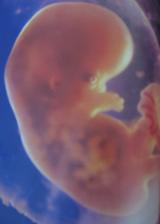

Pupíček se klube na svět

Snažit jsme se začali v září 2006, protože jsme chtěli spíše letní dítko. Hlavně aby nemělo narozeniny jako oboje rodiče v zimě... A protože člověk míní a život mění, jindy to snad ani vyjít nemohlo a čekáme dalšího Ježíška. Ve chvíli, kdy mě chtěl začít pan doktor léčit a předepsal mi prášky, rázem už nebyly potřeba. Ani jsem je nestačila začít brát. Pupíček by měl přijít na svět v půlce prosince, ale věřím, že když už se to takhle povedlo, vydrží s premiérou minimálně přesně na Vánoce 🙂